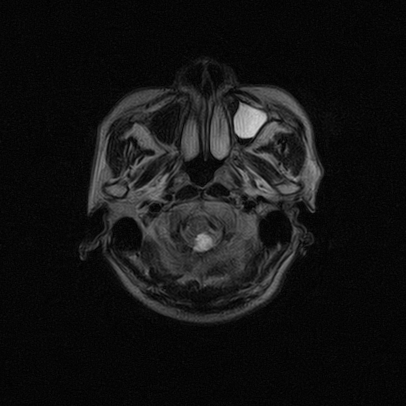

标题: MRI2064:少见病例。男性52,视力下降多年。 [打印本页]

标题: MRI2064:少见病例。男性52,视力下降多年。

四脑室区见混杂信号占位影,脑室系统扩张明显,临近结构显著受压称位,患者52岁,多考虑室管膜瘤可能性大

应该是来源于小脑蚓部的占位,如血管母细瘤或星形细胞瘤

小脑血管母细胞瘤.并外压性脑积水.

小脑蚓部胶质脑膜瘤突入四脑室;肿瘤内见血管流空信号和钙化信号.

比较典型的脉络丛乳头状瘤并脑积水,鉴别小脑蚓部血管母细胞瘤。